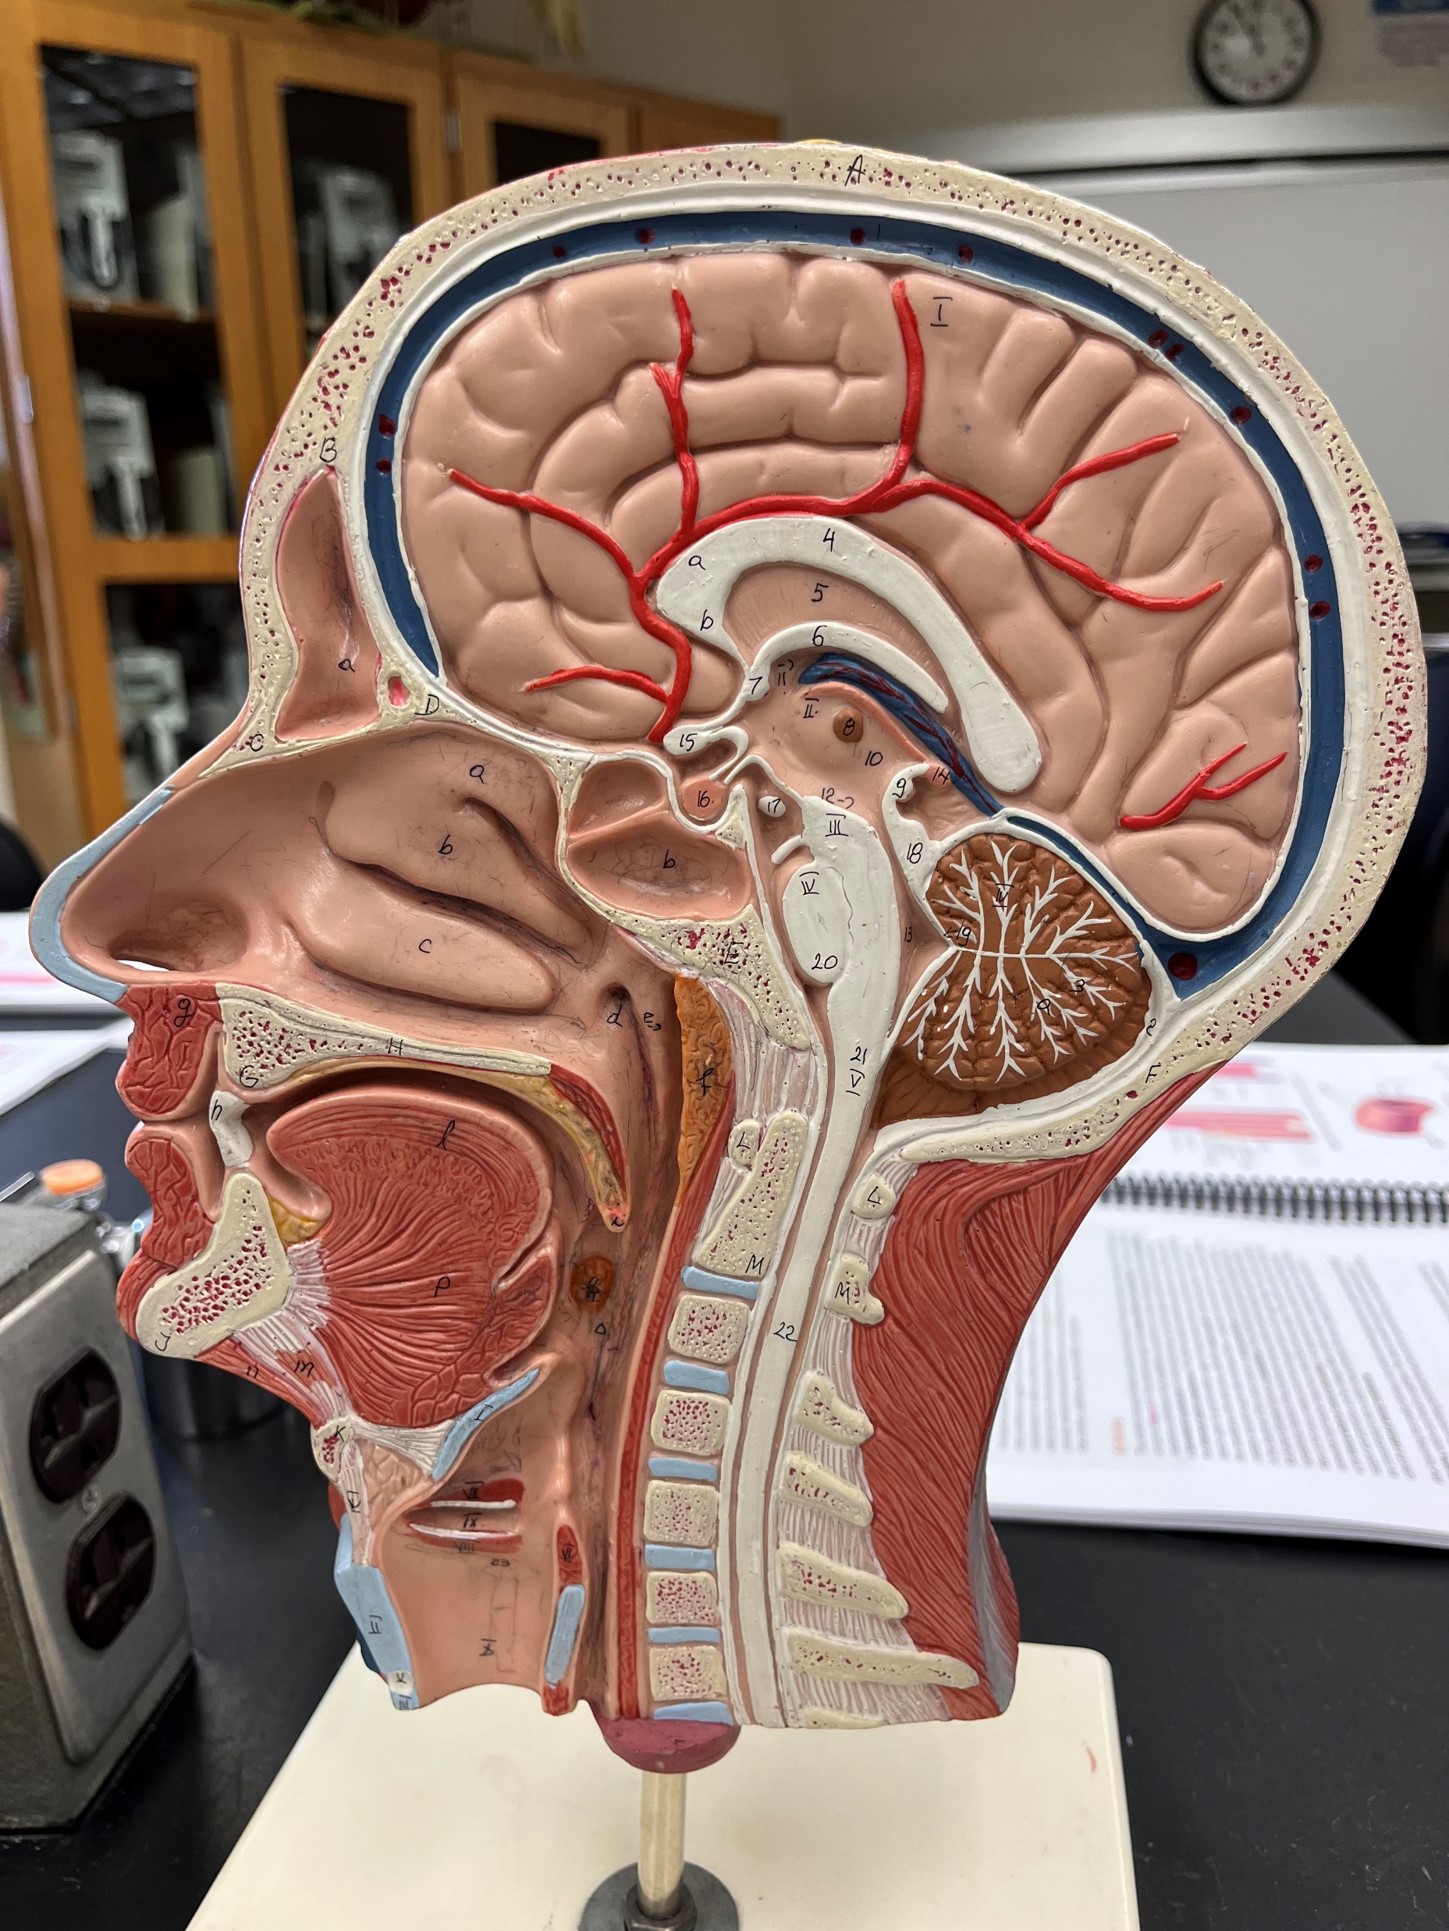

common carotid artery

• An artery of the head and neck.

• Originates from the brachiocephalic trunk (R.) or the aortic arch (L.).

• Supplies the head and neck through its branches.

• Originates from the brachiocephalic trunk (R.) or the aortic arch (L.).

• Supplies the head and neck through its branches.

external carotid artery

• An artery of the head and neck.

• Originates from the common carotid artery.

• Supplies the extracranial structures through its branches.

• Laterally, the anteriormost artery of the neck.

• Originates from the common carotid artery.

• Supplies the extracranial structures through its branches.

• Laterally, the anteriormost artery of the neck.

internal carotid artery

• An artery of the head and neck.

• Originates from the common carotid artery.

• Supplies the cerebrum through its branches.

• Laterally, the middle artery of the neck.

• Originates from the common carotid artery.

• Supplies the cerebrum through its branches.

• Laterally, the middle artery of the neck.

vertebral artery

• An artery of the head and neck.

• Originates from the subclavian artery.

• Supplies the spinal cord, meninges, and neck muscles.

• Laterally, the posteriormost artery of the neck.

• Originates from the subclavian artery.

• Supplies the spinal cord, meninges, and neck muscles.

• Laterally, the posteriormost artery of the neck.

internal jugular vein

• A vein of the head and neck.

• Drains the brain, face, and neck.

• Empties into the subclavian vein.

• Laterally, the anteriormost vein of the neck.

• Drains the brain, face, and neck.

• Empties into the subclavian vein.

• Laterally, the anteriormost vein of the neck.